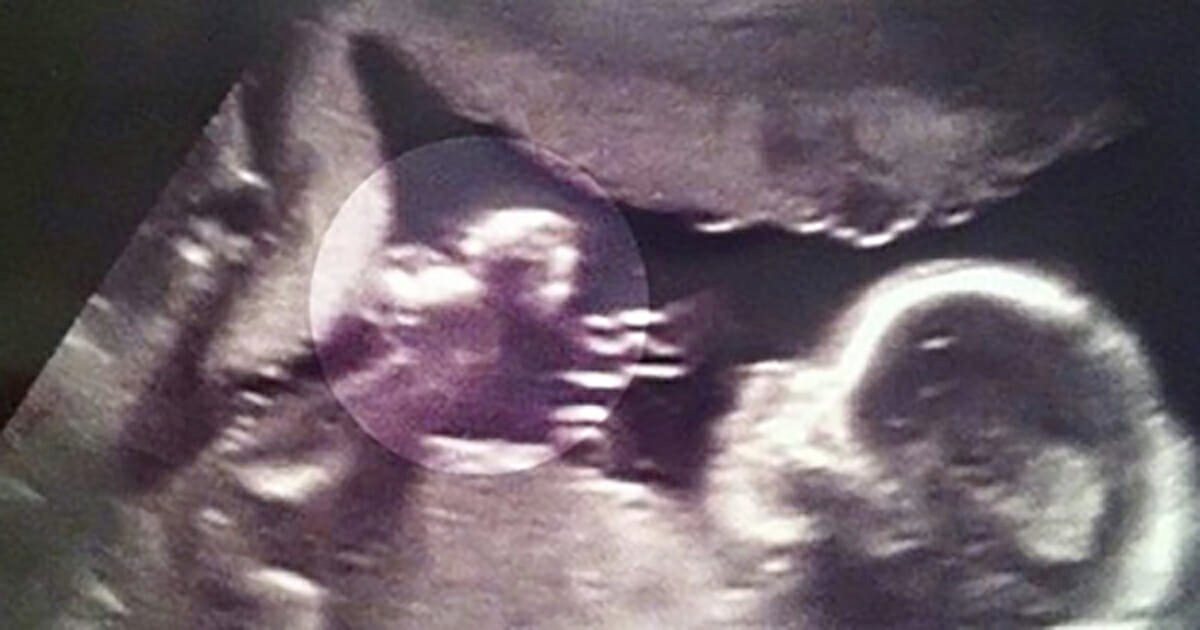

Seeing an image of your unborn child on an ultrasound is such a magical time for any expectant parent. But for Kelly Lewis she wasn’t just blown away by seeing … …